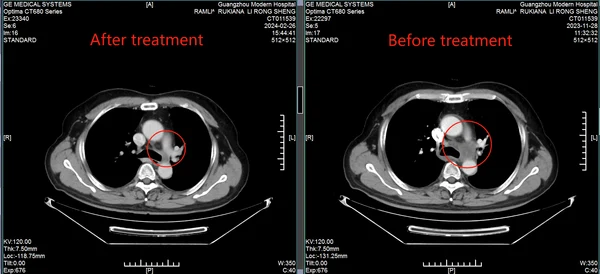

История надежды: Рамли Рукиана из Индонезии побеждает рак легких IV стадии при серьезных сердечных заболеваниях

50-летний пациент с функцией сердца 30% достиг ремиссии благодаря щадящим технологиям в Гуанчжоу

Вызов: двойной диагноз

В ноябре 2023 года у Рамли Рукианы из Батама (Индонезия) появилась необъяснимая охриплость голоса. Обследование в Сингапуре выявило шокирующую правду: рак левого легкого IV стадии с метастазами в лимфоузлы. Опухоль размером 1.7 см усугублялась критическим состоянием сердца - функция составляла всего 30%. Местные врачи не предлагали вариантов, кроме рискованной операции. «Я думал, это конец. Боялся рассказывать семье и готовился к худшему», - вспоминает Рамли.

Лечение: интервенционная терапия вместо скальпеля

Команда клиники разработала персонализированный план: Интервенционная терапия - доставка химиопрепаратов непосредственно в опухоль через катетер под контролем КТ. Преимущества для Рамли: • Нет воздействия на сердце и здоровые ткани. • Отсутствие побочных эффектов: тошноты, слабости, выпадения волос. • Минимальное время в стационаре - возможность работать удаленно. «После процедуры я шутил, что готов лететь домой в тот же день!»

Результат: победа над невозможным

• Через 2 месяца: Опухоль в легком практически исчезла, метастазы в лимфоузлах значительно уменьшились. • Сердечная функция стабилизировалась - лечение не усугубило риски. • Возврат к активной жизни: Рамли общается с пациентами из других стран, используя переводчик, и вдохновляет их своим примером.

КТ-снимки подтвердили: динамика положительная, болезнь отступает

26 февраля 2024 года результаты КТ показали, что опухоль легкого значительно уменьшилась